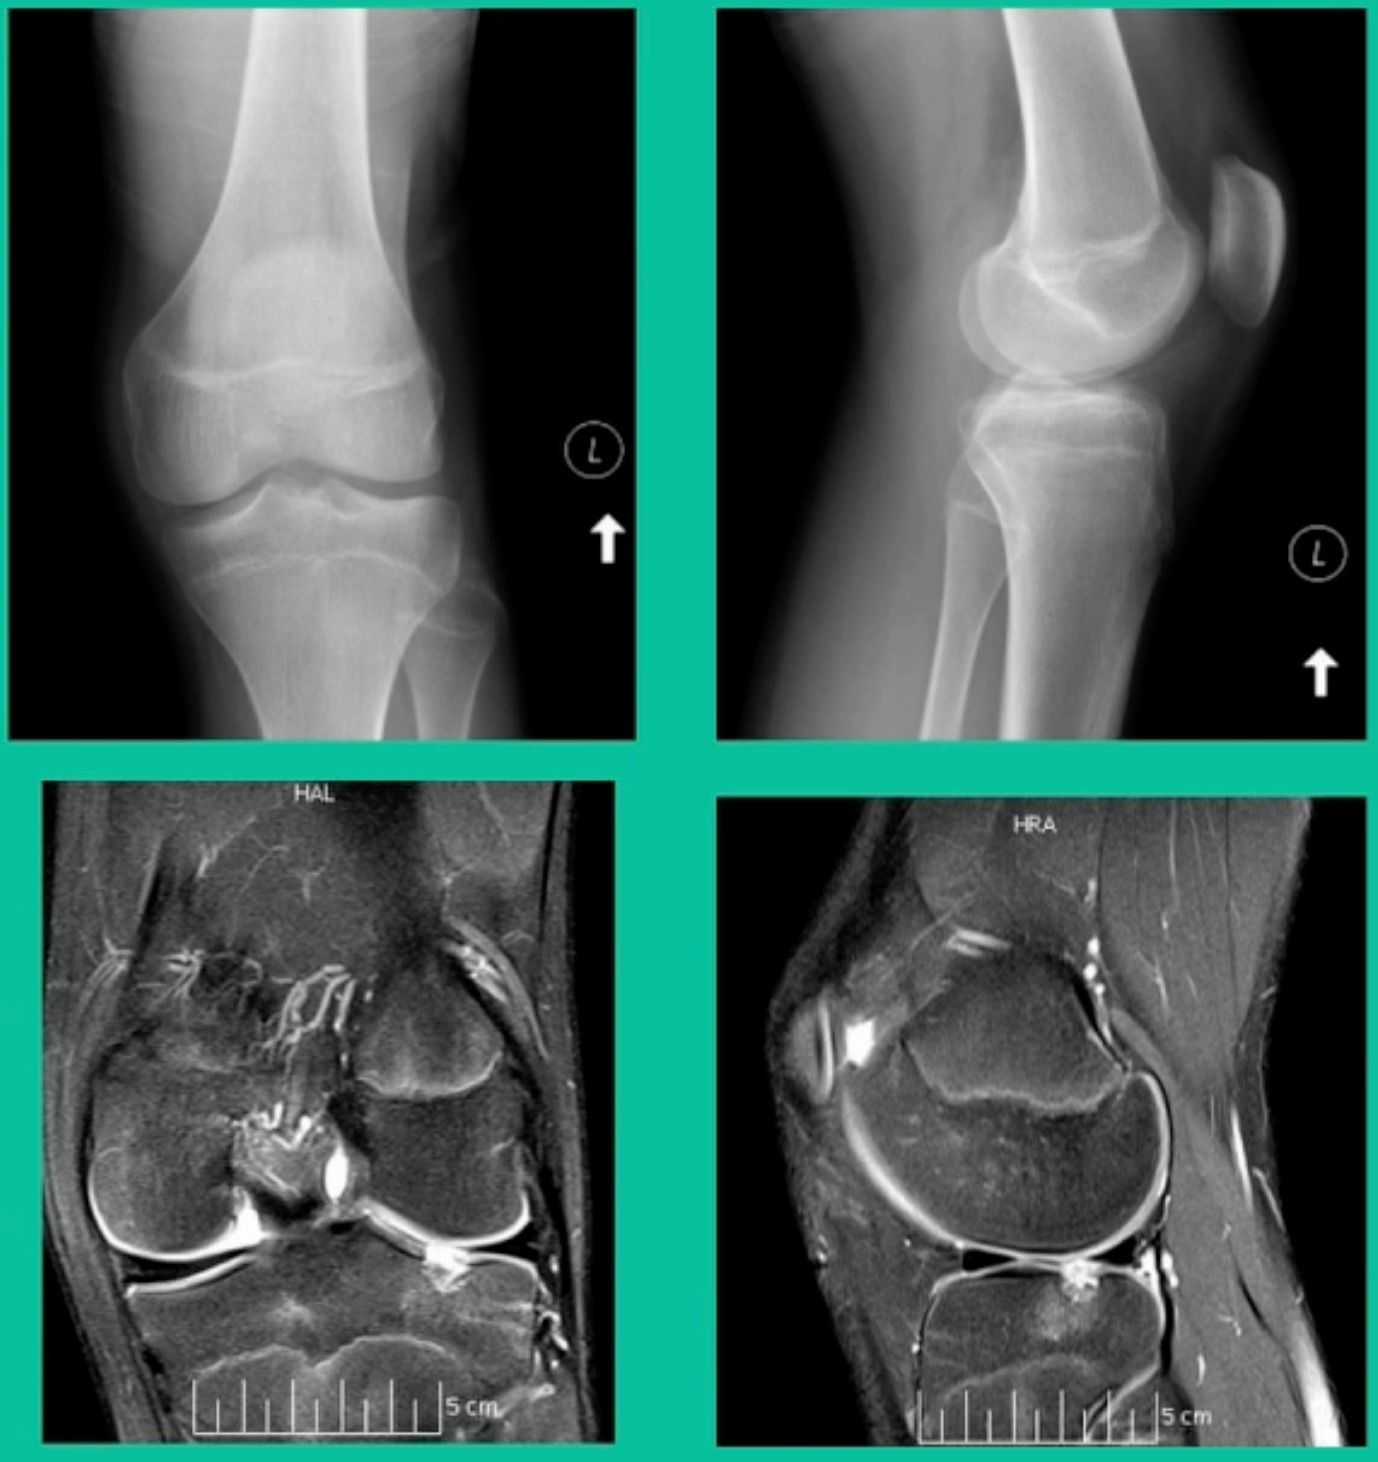

Another case example. 14-year-old male tennis player, 10 months of knee pain (Figure 7A).

This is a Trochlear defect (Figure 7B).

This goes back to metallic screw fixation, because this one is macroscopically unstable. That is a fracture non-union. That’s an atrophic non-union. Debride it, curette it, drill it, and thenwe use metal screws because it’s macroscopically unstable.

However, in this instance, we did take the screws out.

He was back to everything at 16 weeks and, at two years, he had no further symptoms. How do these do? There’s plenty of literature that shows that metallic screw fixation for unstable OCD, not just in juveniles, but in adults, will lead to reliable fixation. It’s a four-month process. They get back to everything, and they rarely have problems downstream.